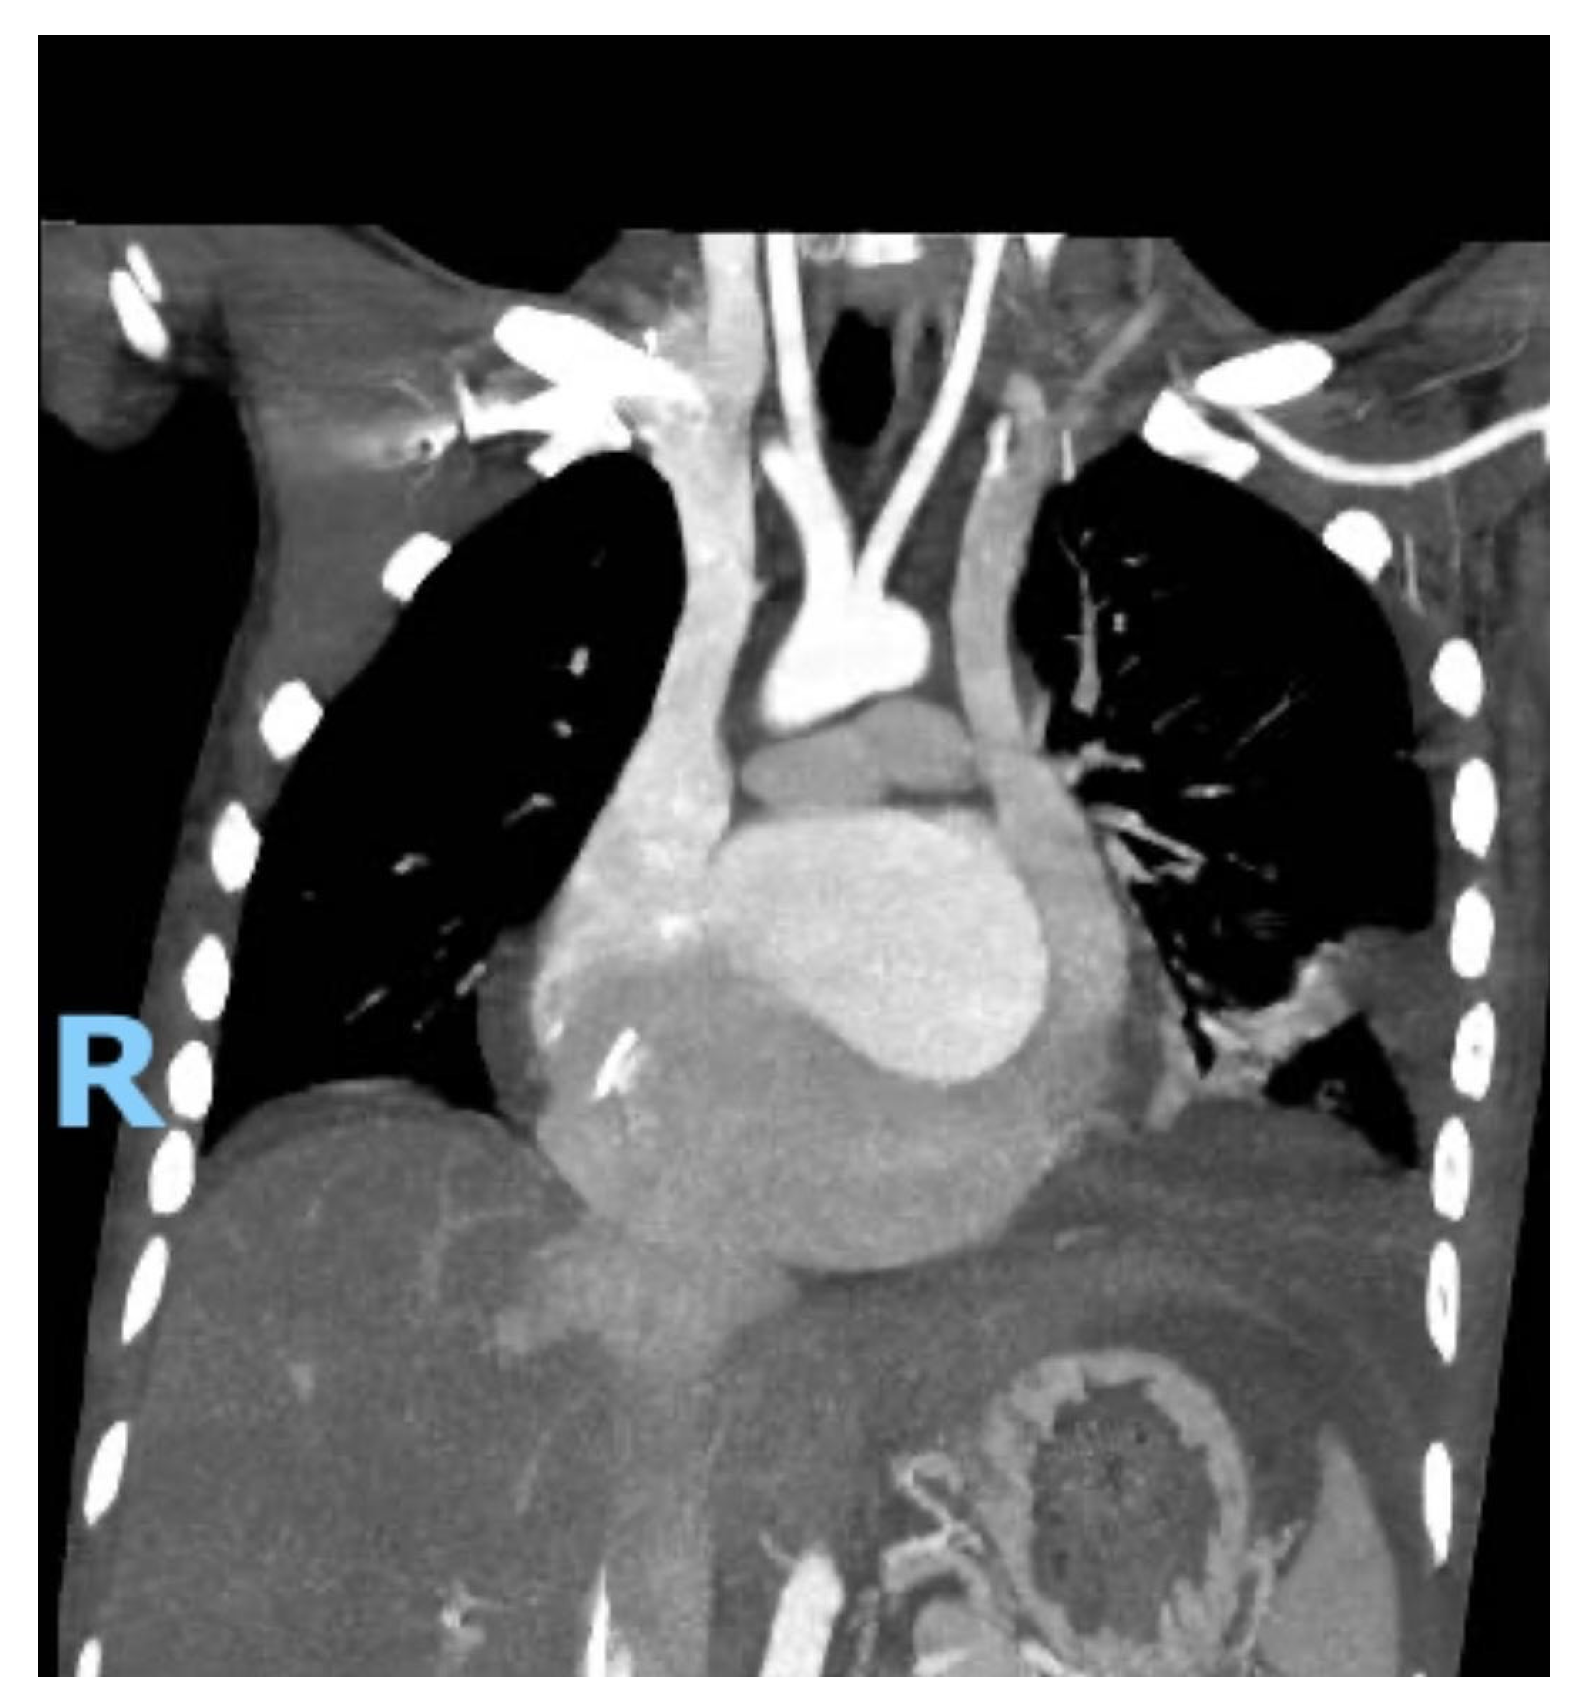

A 27-year-old Bengali male with a known history of Wilson’s disease presented to the emergency department with dyspnea, fatigue, and chest discomfort. Initial diagnostic work-up included an electrocardiogram (ECG), which revealed complete heart block with an escape rhythm at approximately 40 beats per minute. Transthoracic echocardiography (TTE) showed biatrial dilation, a severely dilated CS, mild left ventricular (LV) dilation, and a left ventricular ejection fraction (LVEF) of 45% (Fig. 1).

Figure 1: Transthoracic echocardiography showing a severely dilated coronary sinus.